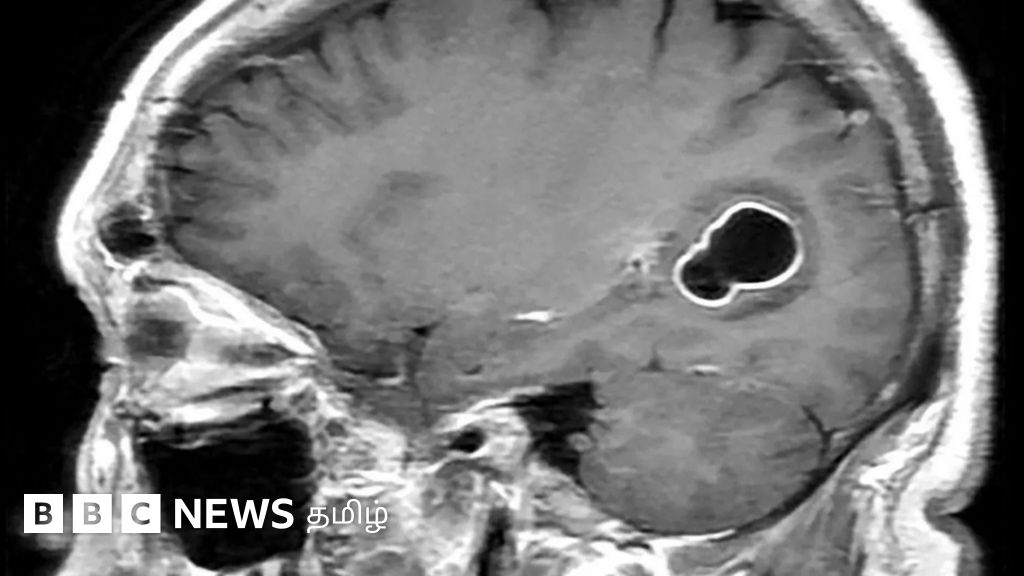

நமது மூளைக்குள் புழுக்கள் எப்படி நுழைகின்றன? தடுப்பதற்கு என்ன செய்ய வேண்டும்? 🕑 Wed, 20 Mar 2024

நமது மூளைக்குள் புழுக்கள் எப்படி நுழைகின்றன? தடுப்பதற்கு என்ன செய்ய வேண்டும்?

அமெரிக்காவில் அடிக்கடி ஒற்றைத் தலைவலியால் அவதிப்பட்ட 52 வயது நபர் ஒருவரின் மூளையில் நாடாப்புழுக்கள் இருப்பது கண்டறியப்பட்டிருக்கிறது.